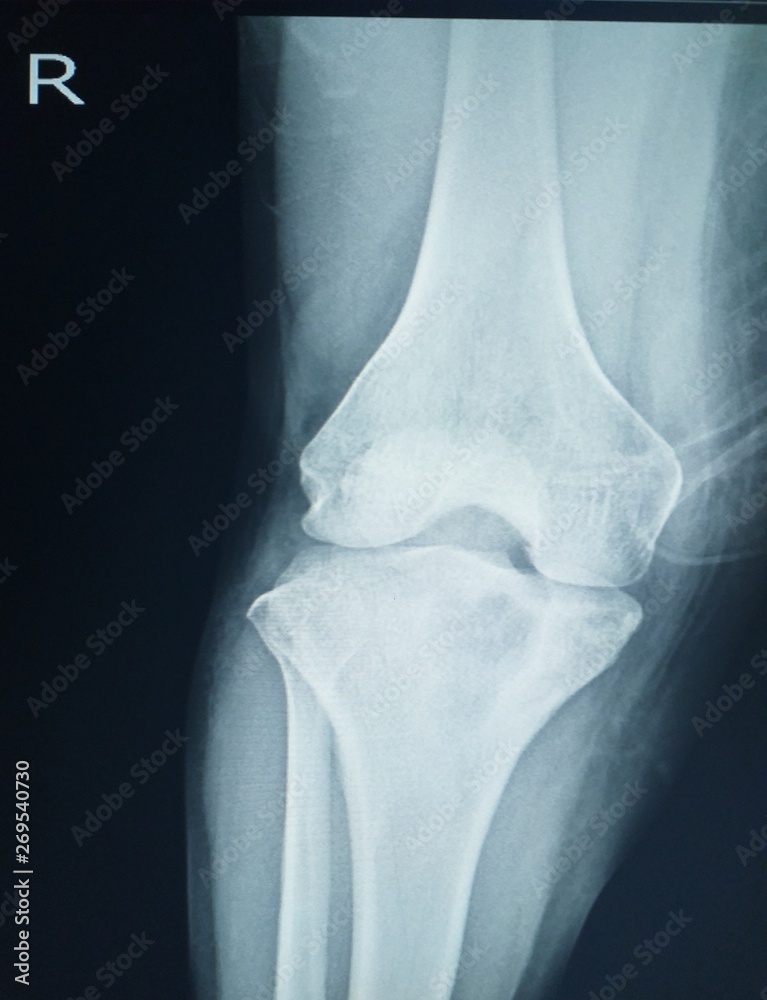

Xray Knee showing Localized mild osteosclerosis plus 4.5 cm lytic Is Periosteal Reaction Normal periosteal reaction refers to the elevation of periosteum from cortical bone and the subsequent deposition of new bone in this. in this article, we review the histologic underpinnings of normal periosteum, the normal anatomic distribution of periosteum, periosteal. if we see a solid pattern of periosteal reaction, we can be fairly confident that we are dealing with. Is Periosteal Reaction Normal.